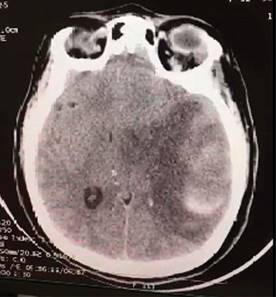

A su ingreso en UCI se recibe paciente bajo intubación orotraqueal y ventilación mecánica invasiva bajo sedación, a su llegada se realiza tomografía de cráneo simple, la cual muestra: hematoma parenquimatoso temporoparietal izquierdo, de 55 × 88 × 50 mm (aproximadamente 38 cm3), edema cerebral, colapso de sistema ventricular lateral ipsilateral y desviación de la línea media 9 mm aproximados (Figura 2), es valorada por neurocirugía, descartándose manejo quirúrgico de urgencia, se inicia terapia osmolar con soluciones hipertónicas al 7.5%, medidas antitrombóticas, y resto de manejo con base en metas internacionales de paciente neurocrítico, manteniendo evolución estacionaria, la nueva tomografía de cráneo cinco días después de su ingreso (Figura 3) muestra infarto cerebral en hemisferio izquierdo y sangrado intraparenquimatoso antiguo, el cual se encuentra en procesos de reabsorción, además de edema cerebral severo, por lo que amerita intervención por neurocirugía, donde se realiza craniectomía parietofrontal izquierda, para mejoría de compliance cerebral. La TAC de control posterior a evento quirúrgico (Figura 4) reporta disminución del edema.

Figura 3: Tomografía computarizada de cráneo con presencia de sangrado intraparenquimatoso en proceso de reabsorción y edema cerebral.